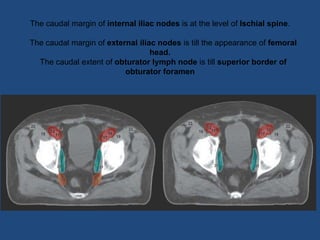

The caudal margin of internal iliac nodes is at the level of Ischial spine.

The caudal margin of external iliac nodes is till the appearance of femoral

head.

The caudal extent of obturator lymph node is till superior border of

obturator foramen